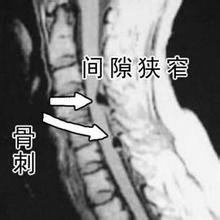

骨刺是骨质增生的主要表现,但是严谨来说,医学上并没有称为骨刺的疾病,骨刺就是一种关节和骨骼正常退变老化的表现。40岁后,90%的人负重关节或多或少产生增生性改变,长出骨刺。一般来说,骨刺悄悄生长并不影响生活,患者并无临床表现,只有当骨刺发展到一定程度,开始累积压迫到周围神经和血管,并造成局部无菌性炎症时,才会出现肿胀、积液、疼痛等临床症状。

在人体的“骨骼大厦”中,胶原蛋白是钢筋,钙、镁、磷等骨质就是水泥。30岁后,胶原蛋白流失加剧,胶原框架老化变细、变脆甚至断裂,出现缺口;钙、镁、磷等骨质无法正常沉积在骨骼上,从缺口中游离出来;随着肢体的活动和负重,游离的骨质慢慢堆积在活动频繁、承重量大的关键部位(如颈椎、腰椎、膝关节、足跟),骨刺由此产生。